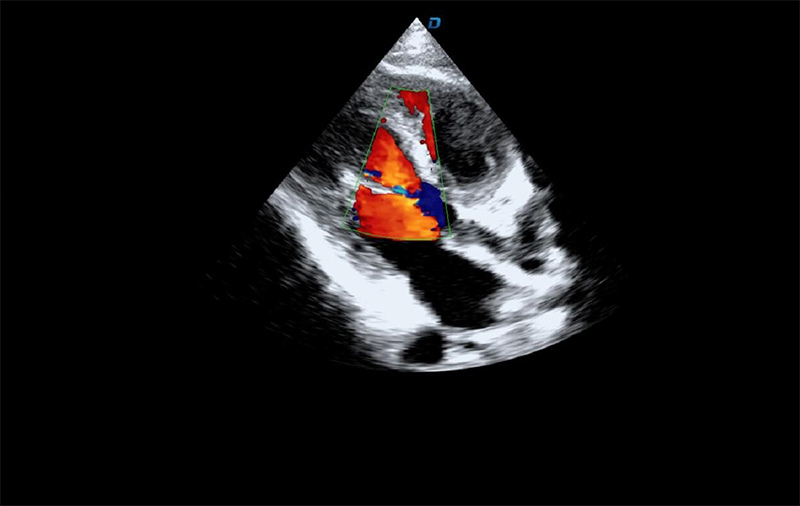

心臟彩超機(jī)檢查

有些心臟病會(huì)引起心臟電活動(dòng)的改變,但是有些心臟的疾病卻不影響心電,而只影響心臟本身的結(jié)構(gòu)。比如心臟擴(kuò)大,心臟收縮無(wú)力,心臟的瓣膜關(guān)閉不嚴(yán)密,這些疾病的診斷及發(fā)現(xiàn)更多的依賴于心臟彩超,這些病變一般不隨癥狀的緩解而緩解。心臟超聲心動(dòng)圖,不需要開胸,就可以看到心臟的大小、內(nèi)部結(jié)構(gòu)、瓣膜運(yùn)動(dòng)情況等。除了探頭壓迫可能會(huì)有疼痛或不適感外,對(duì)患者沒有任何創(chuàng)傷。

臨床上,心臟超聲心動(dòng)圖主要用于對(duì)各種先心病、心臟瓣膜病的診斷;各種心肌病、心包疾病的診斷和心臟功能的評(píng)估。部分嚴(yán)重肺氣腫、胸廓畸形等患者,因?yàn)槌晥D像質(zhì)量欠佳而診斷效果受到一定限制。